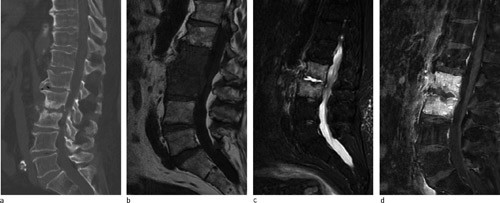

En mann i 70-årene ble lagt inn på Medisinsk avdeling med sepsis forårsaket av Streptococcus pneumoniae og ryggsmerter, tolket som lungebetennelse. Han ble initialt behandlet med intravenøs penicillin og gentamicin og utskrevet med perorale antibiotika. En uke senere ble han på ny innlagt med økende ryggsmerter, feber og stigende infeksjonsparametre. Det var ingen nevrologiske utfall. På bakgrunn av sykehistorien og sparsomme funn ved auskultasjon og røntgen thorax, ble CT columna, så MR rekvirert. CT viste uregelmessig kontur av nedre og øvre dekkplater i L2/L3, subkondrale destruksjoner og nedsatt skivehøyde (a). På standard T1-vektede (b) og STIR (short τ inversion recovery)-bilder på MR (c) ses utbredt ødem i L2, L3 og i det paravertebrale bløtvevet. På serien med kontrast med fettsuppresjon ses randkontrastoppladning i selve skiven (d). Disse funnene sammen med de kliniske funnene er forenlig med bakteriell spondylodiskitt.